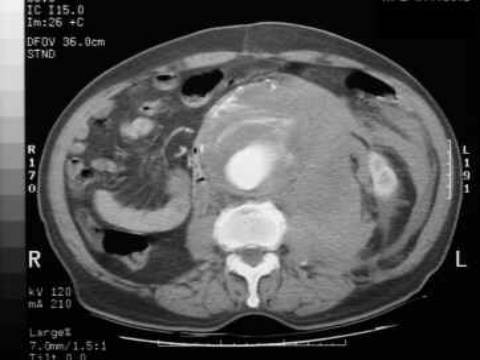

The abdominal aorta is the most common site of an arterial aneurysm. Abdominal aortic aneurysms (AAA) are usually located below the renal artery (infrarenal aorta).

The abdominal aorta is 1-3 cm in diameter in most individuals, and a diameter >3 cm at the level of the renal arteries is considered to be an aneurysm. Unlike thoracic aortic aneurysms, an AAA involves all aortal layers and does not create an intimal flap or false lumen. An AAA typically occurs in people aged >60 years and occurs at a higher rate in smokers, men, and people with a history of coronary artery disease.

Symptoms

Patients typically have few symptoms with AAAs, which are usually incidentally found on screening ultrasound or CT scan of the abdomen. Physical examination can reveal a pulsatile abdominal mass at or above the level of the umbilicus. Once the aneurysm ruptures, only about 50% of the patients survive to come to the hospital. They present with profound hypotension, abdominal or back pain followed by syncope, and possible pulsatile mass on examination. An AAA can rupture into the retroperitoneum and create an aortocaval fistula with the inferior vena cava, leading to venous congestion in retroperitoneal structures (e.g. bladder). The fragile and distended veins in the bladder can rupture and cause gross hematuria (as in this patient).

The symptoms and signs can also mimic other abdominal pathologies, such as renal colic, mesenteric ischemia, pancreatitis, diverticulitis, and biliary disease. This patient's acute onset of symptoms, age, and profound hypotension suggest ruptured AAA, which must be ruled out before the other etiologies. He should be immediately taken to the operating room for emergent surgical repair of the ruptured AAA. Mortality with this condition is approximately 50%, so early recognition and operative intervention is essential.